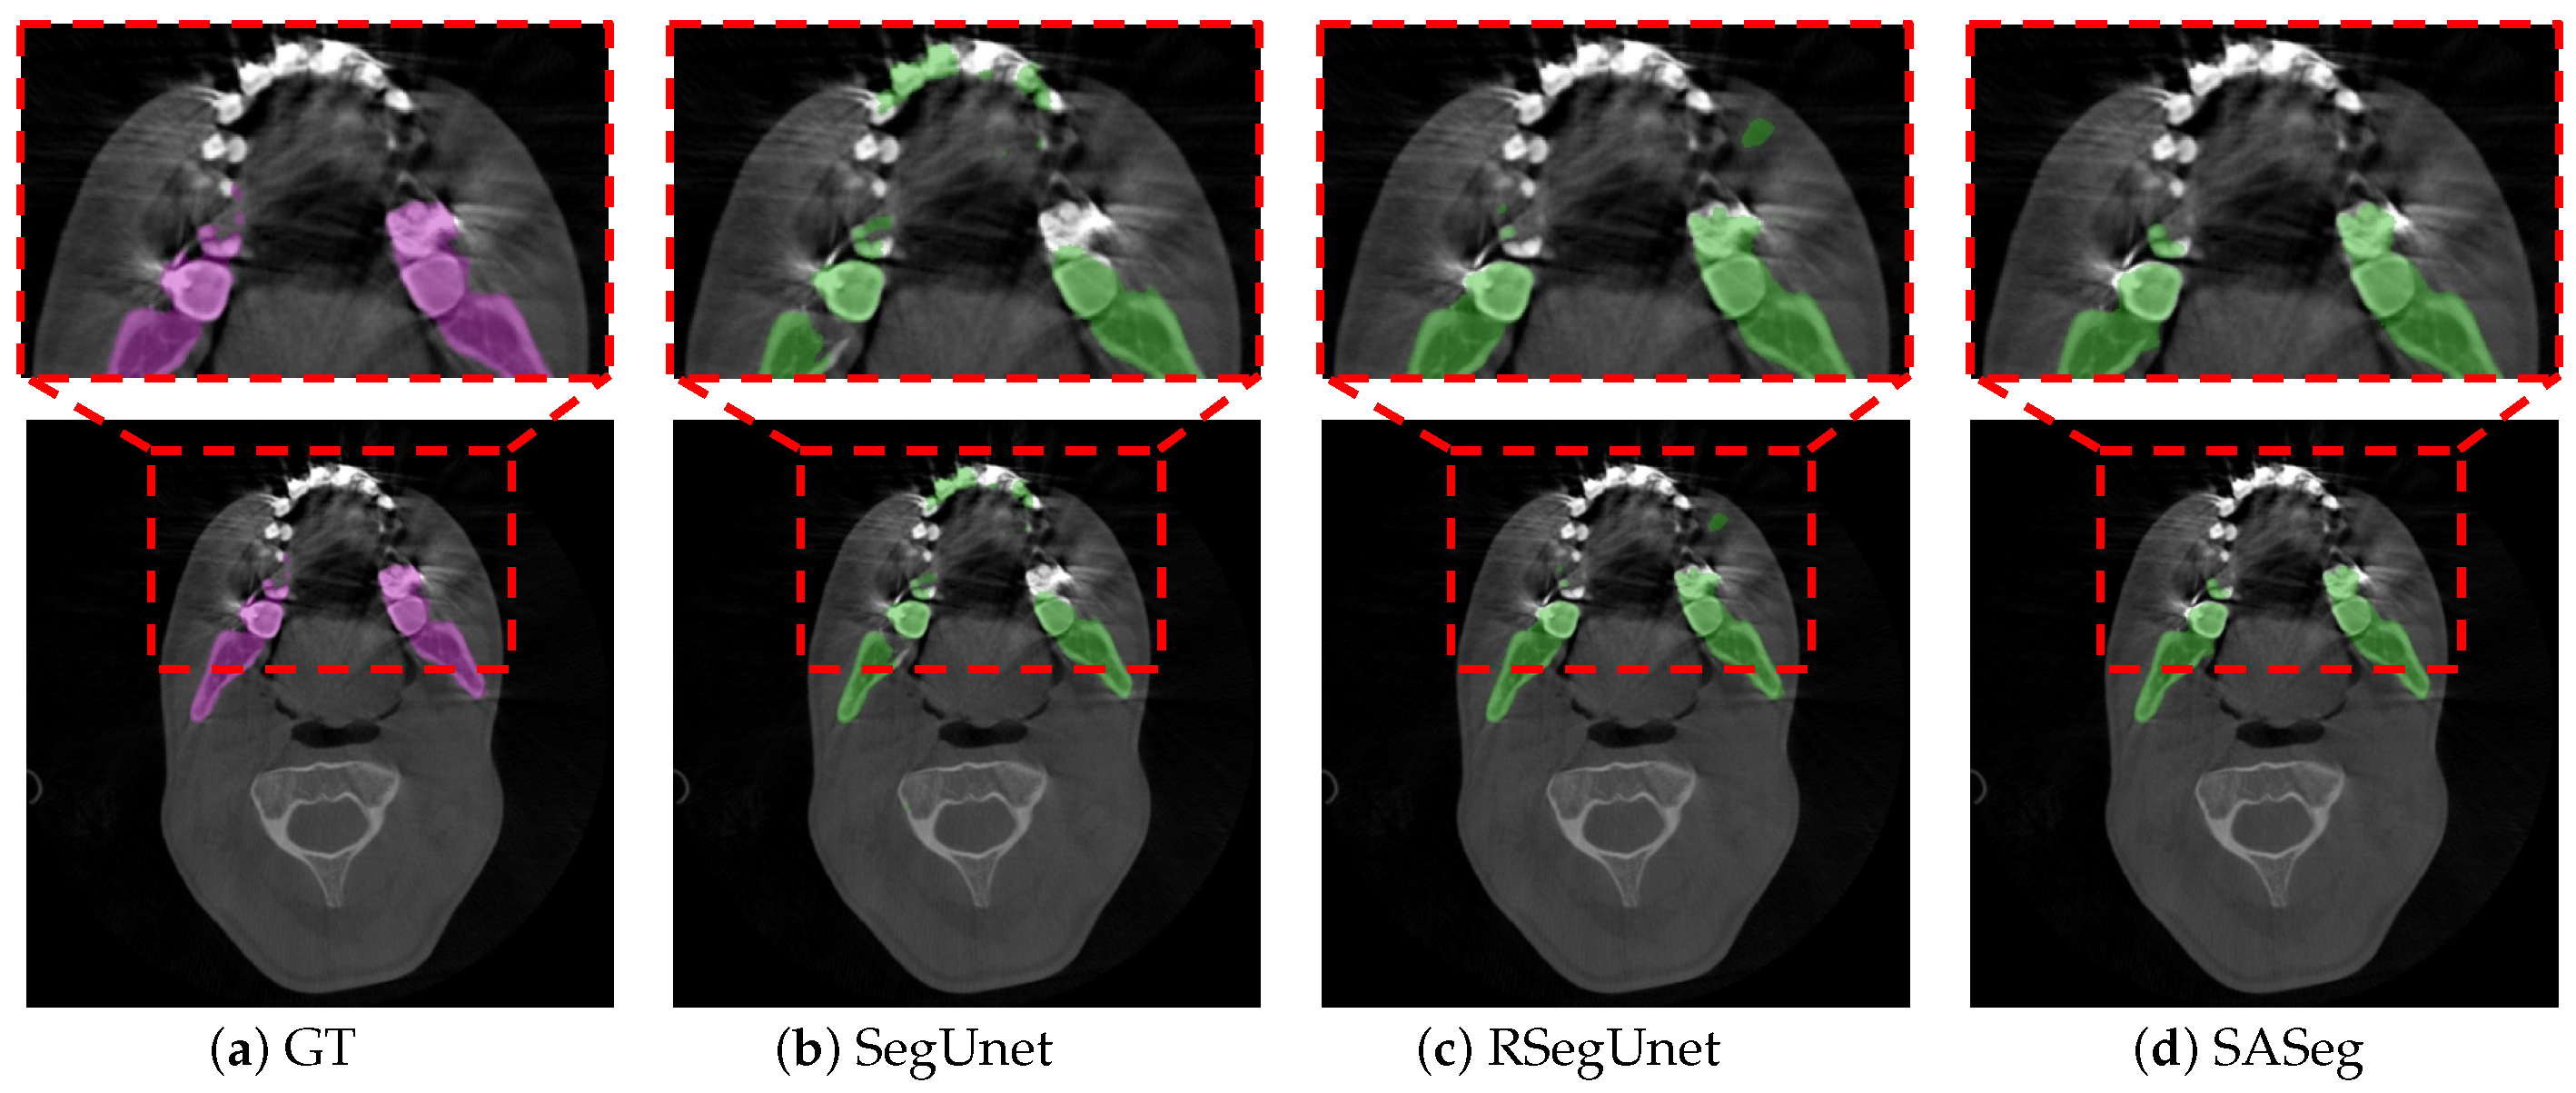

3. Results

3.1. Method Comparison